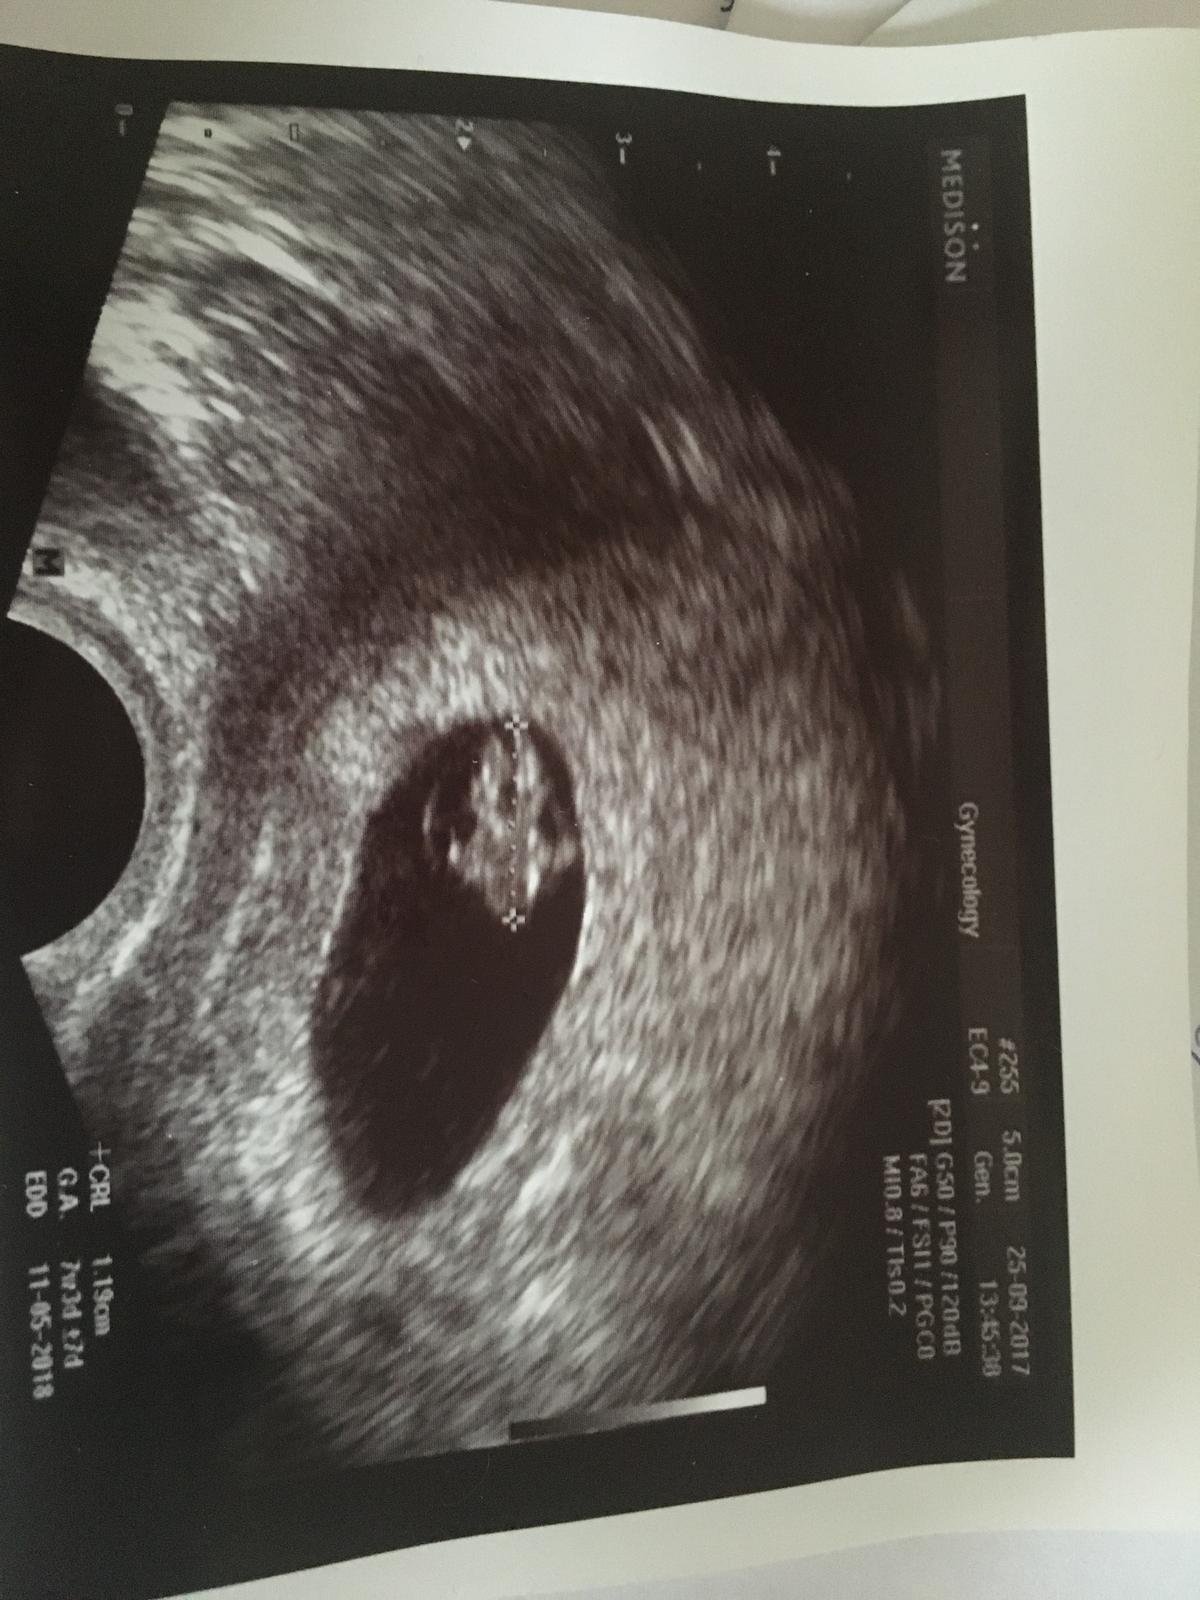

Podle MS dnes 7+0, podle UTZ 7+3, srdíčko tluče, je to zvláštní pocit, pořád tomu nevěřím, že jsem se skoro ve 39 letech (příští týden) konečně dočkala. Držte nám palce, ať se fazole ještě dalších 33 týdnů drží uvnitř 😉🍀😍.